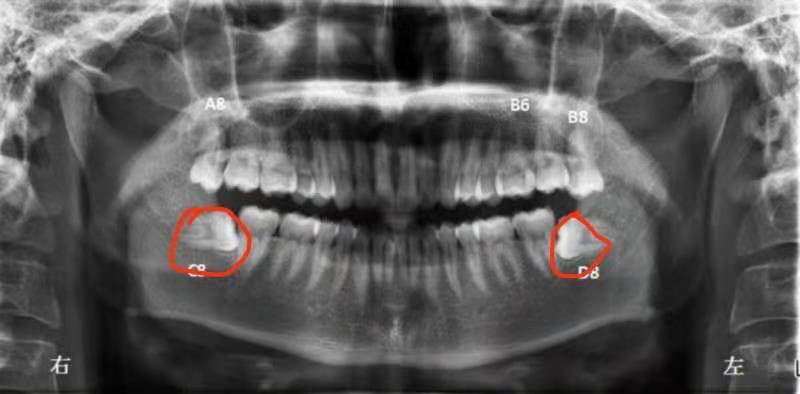

掹智慧齒尤其是掹阻生智慧齒(如下圖為阻生智慧齒),使用傳統的切割方法,留下的傷口會比較大。目前業界已經出現微創無疼掹智慧齒的方法:主要采取ct機,拍攝阻生智齒的位置,結合相應的數據,為醫生准確開刀提供支持。醫生據此可以精確,微創,傷口小,迅速的拔除牙齒,從而實現微創無疼拔除智慧齒。

微創無疼拔智慧齒是否每個醫生都具備此項手術能力?並非如此,首先這需要醫生懂得觀察x光提供的數據,能夠快速而准確的分析智慧齒周圍的生長情況,牙神經的分布情況,並且在操作過程中能夠快速辨別圖形與對應實際的位置,操作快速而簡練。